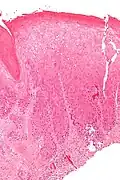

Micrograph of differentiated vulvar intraepithelial neoplasia. H&E stain.

Differentiated vulvar intraepithelial neoplasia also known as VIN Simplex: is associated with vulvar dermatoses such as lichen sclerosus. It is associated with atypia of the squamous epithelium.

The type and distribution of lesions varies among the two different types of VIN. In the Usual type VIN, seen more frequently in young patients, lesions tend to be multifocal over an otherwise normal vulvar skin. In the differentiated type VIN, usually seen in postmenopausal women, lesions tend to be isolated and are located over a skin with a vulvar dermatosis such as Lichen slerosus.[4]